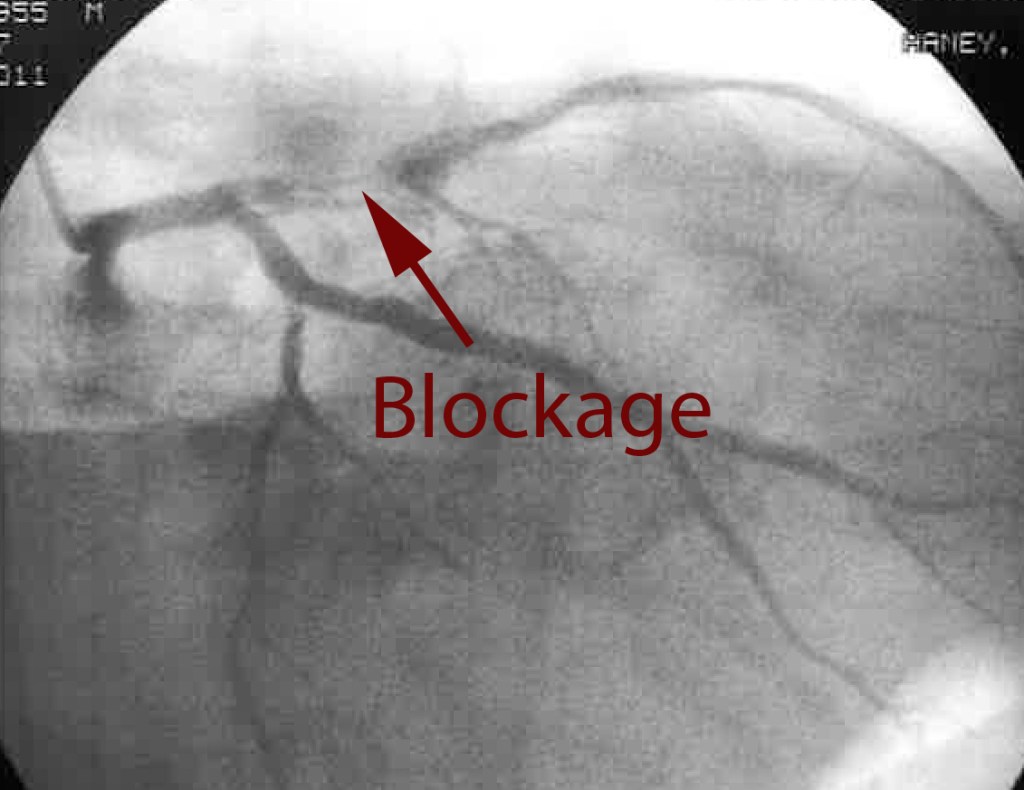

So how did all this surgery business come about? Well grab a cup of tea and a biscuit and I shall begin. Ok I don’t know… I have to believe that it was just a combination of bad eating for… Continue reading